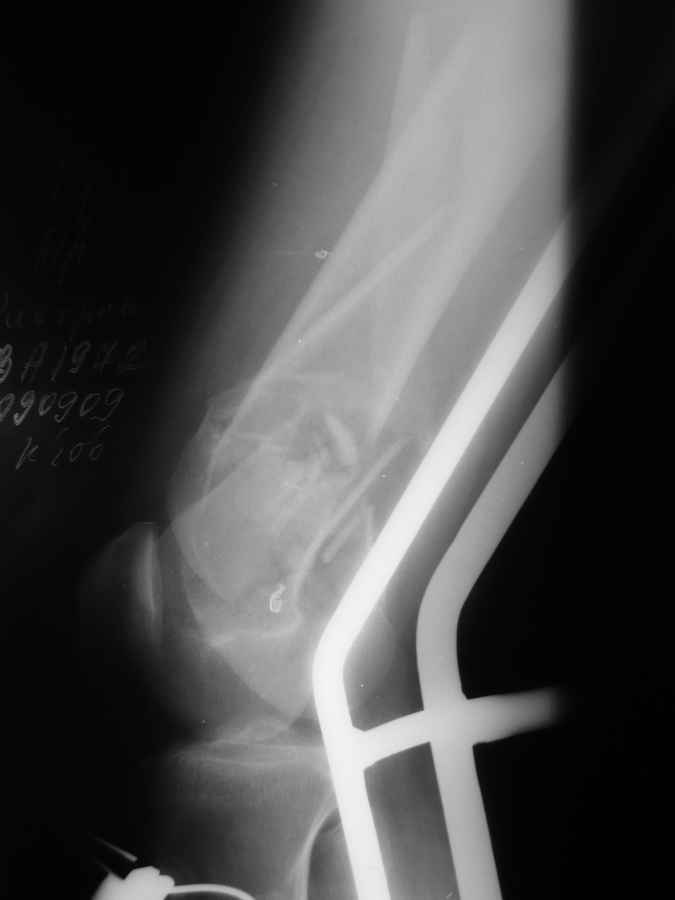

Это перелом не нижней трети, а дистального суставного конца, с распространением на диафиз. Что-то между C2 и C3. Но пока ближе к C2 по увиденному - вторую проекцию еще не показали.

На профиле стало видно, что открываться придется, это перелом C3, хотя можно назвать и C2+, т.е. с еще и фронтальным раскалыванием одного мыщелка. Надо сделать медиальную артротомию, ступеньку на внутреннем мыщелке устранить, ввести либо несколько временных спиц спереди назад, или сразу винт вдоль эллипса мыщелка. А дальше как выше написано - дистрактор, и штифтовать. Учитывая наличие открытого колена - вполне уместно ретроградно.

Вообще насчет пластины думали... но если открыться то рассыпится все... LISS можно но тоже тяжело представить...

Бесспорно, предлагаемый ретроградный метод имеет свои преимущества, но имеется опасность при манипуляции интрамедуллярным гвоздем расколоть мыщелки.

Раскол можно предупредить шурупами, но короткий дистальный фрагмент навряд ли позволит добиться адекватной стабильности конструкции. Стандартные гвозди не рассчитаны для таких переломов, и если все таки желаете провести фиксацию гвоздем, тогда надо заказывать специальный custom made nail т.е. с расширенной возможностью дистальной блокировки.